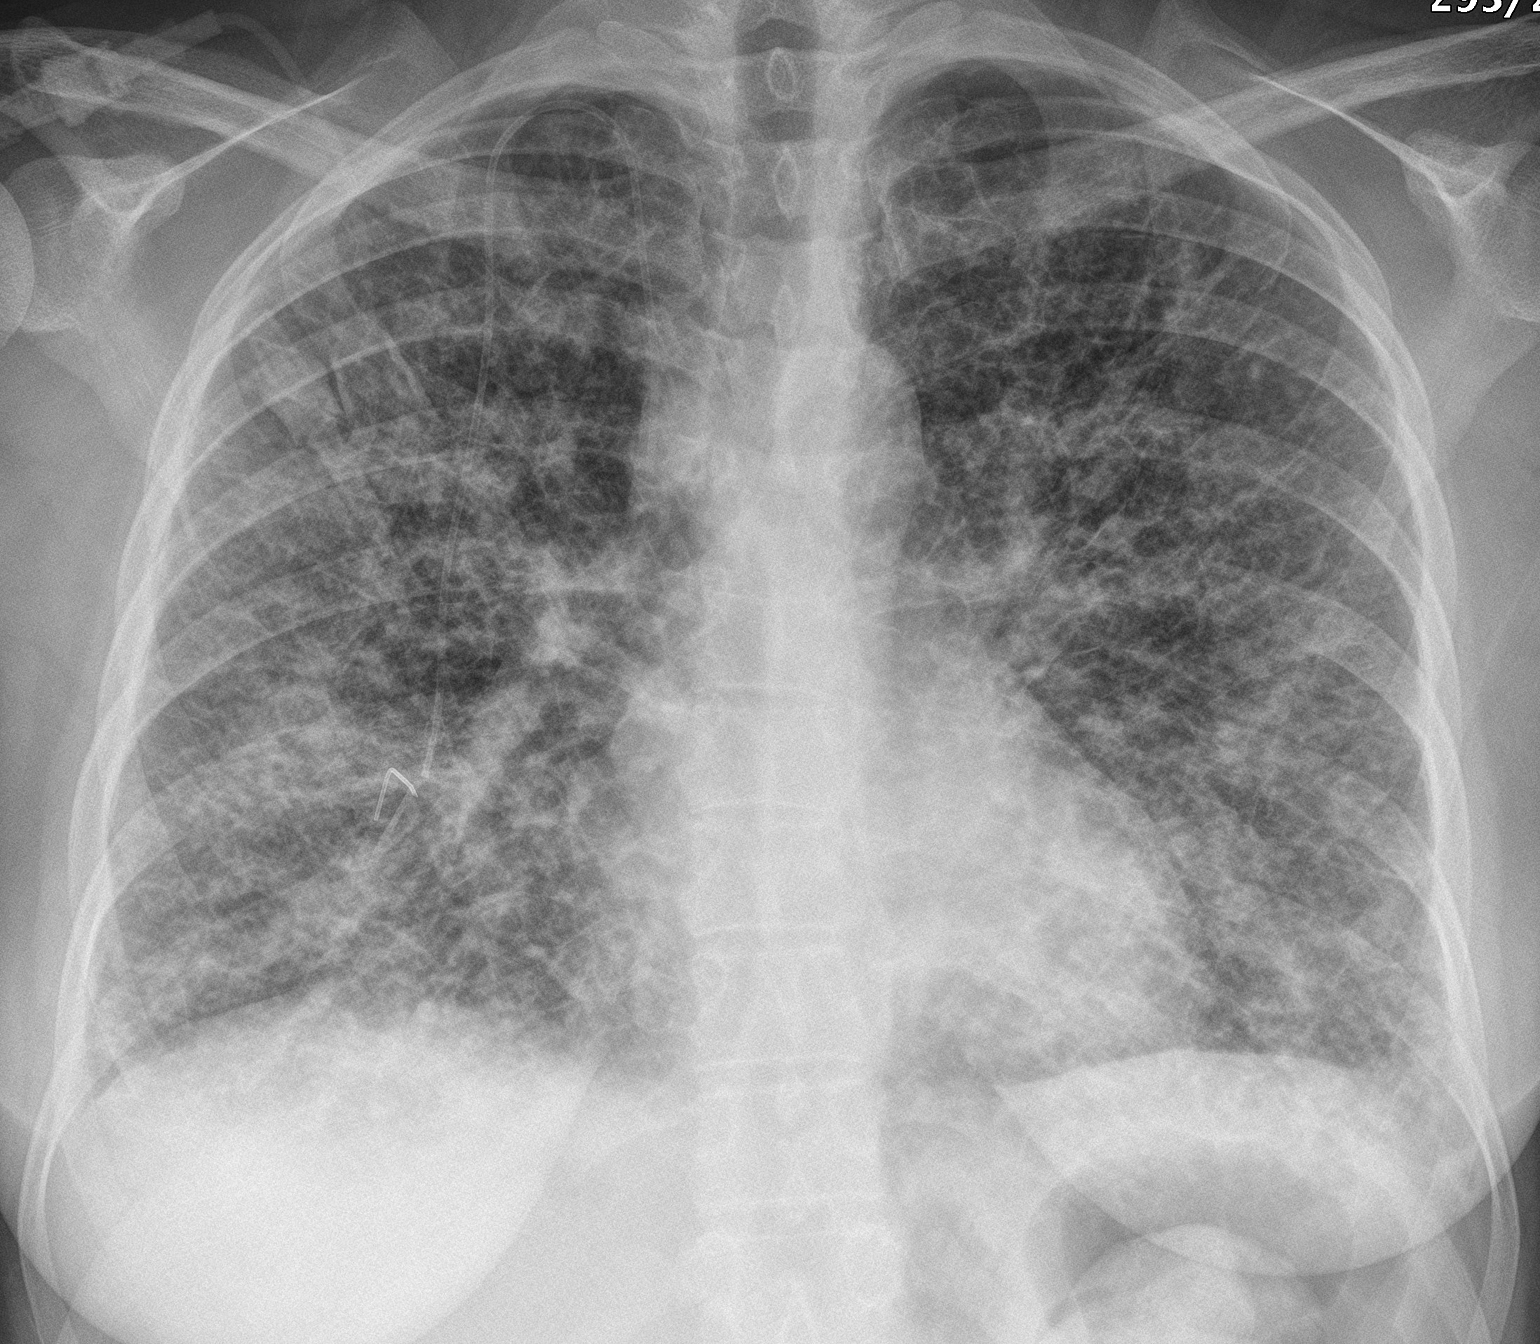

Gallery Lung Cancer Mets Lymphangitic 4 PA

Lymphangitic 4 PA